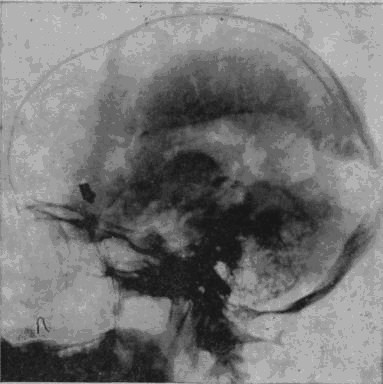

«Младший лейтенант Засецкий, 23 лет, получил 2 марта 1943 года пулевое проникающее ранение черепа левой теменно-затылочной области. Ранение сопровождалось длительной потерей сознания и, несмотря на своевременную обработку раны в условиях полевого госпиталя, осложнилось воспалительным процессом, вызвавшим слипчивый процесс в оболочках мозга и выраженные изменения в окружающих тканях мозгового вещества».

Рис. 1а. Рентгеновский снимок черепа больного Засецкого после введения воздуха в желудочки мозга (пнеймоэнцефалограмма). На нем можно видеть резко расширенный левый боковой желудочек и скопление воздуха в подоболочечных пространствах мозга теменно-затылочной области левого полушария

Осколок внедрился в вещество задних, теменно-затылочных отделов мозга и разрушил мозговую ткань этой области.

Ранение осложнилось воспалительным процессом; он не распространенный, местный, ограничен лишь областями мозга, примыкающими к непосредственному месту ранения, но теменно-затылочные отделы левого полушария, отделы, так тесно связанные с анализом пространственного мира, необратимо повреждены, и уже начинается процесс образования рубцов, который неизбежно повлечет за собою частичную атрофию расположенных вблизи ранения участков мозгового вещества.

И через десять лет после ранения – еще одна выписка из истории болезни, на этот раз сделанная на основе рентгенограммы.

В спинномозговой канал введен воздух. Он поднялся вверх, заполнил контуры желудочков мозга и те пустоты, которые образовались в результате сморщивания вещества отделов мозга, непосредственно примыкающих к месту ранения. «Процесс рубцевания вызвал атрофические изменения в левом боковом желудочке. Стенки его подтянуты к поверхности мозга, подоболочечные пространства резко расширены. Значительный местный атрофический процесс».

Ранение вызвало местную атрофию мозгового вещества левой теменно-затылочной области.